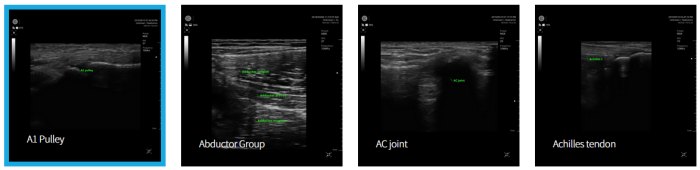

Handheld Ultrasound Devices for Clinical Value - MSK - Medical / Health Care - Clinical Services

A 1 pulley.